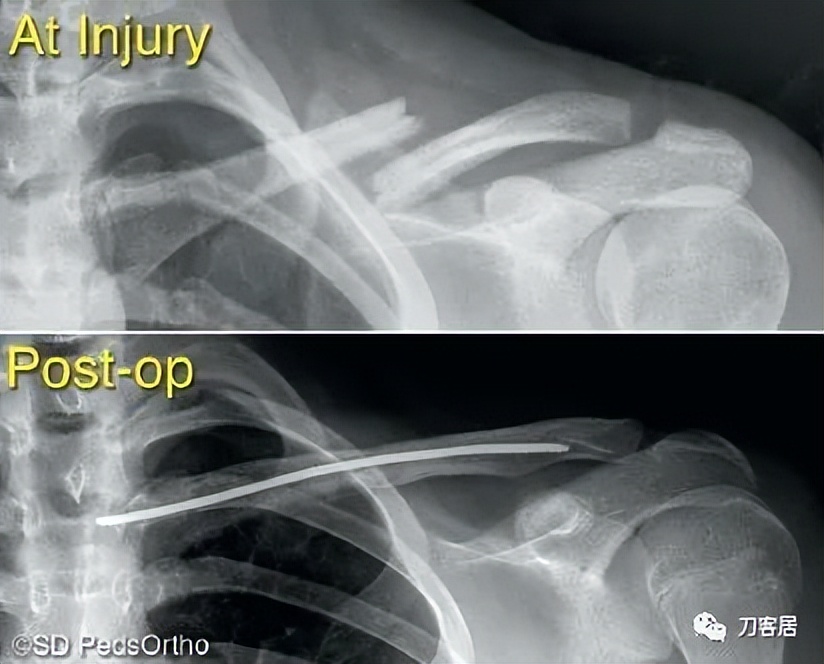

When surgical fixation is potentially required (Type IV, V, or VI injuries), controversy exists as to the optimal fixation technique with some favoring Kirschner wires, others hook plates, pre-contoured lateral clavicle plates, coracoclavicular fixation devices, or a combination thereof (Table 6-3). In the rare circumstance where pin fixation is used, we advocate significantly bending the pin outside the skin to minimize wire migration and weekly clinical evaluations until the pins have been removed (typically 3-4 weeks). The literature indicates that there can be significant complications from pin migration, including death. We believe each of these cases must be approached on an individual basis based on the size and comminution of the fracture fragments.

当需要手术固定时(IV、V或VI型骨折),采取何种固定技术存在争议,有人喜欢用克氏针,另有人喜欢钩板、预弯外侧锁骨板、喙锁固定装置或它们的组合(表 6-3)。在罕有的髓内针固定时,我们主张将针的一端折弯留置皮肤外侧,以防固定针移位,并且每周随访直至固定针去除(一般需要 3-4 周)。文献表明,固定针移位可能会导致严重的并发症,甚至死亡。我们认为,每个病例都应该根据骨折粉碎程度以及骨折块的大小,遵循个体化治疗原则,决定治疗方案。